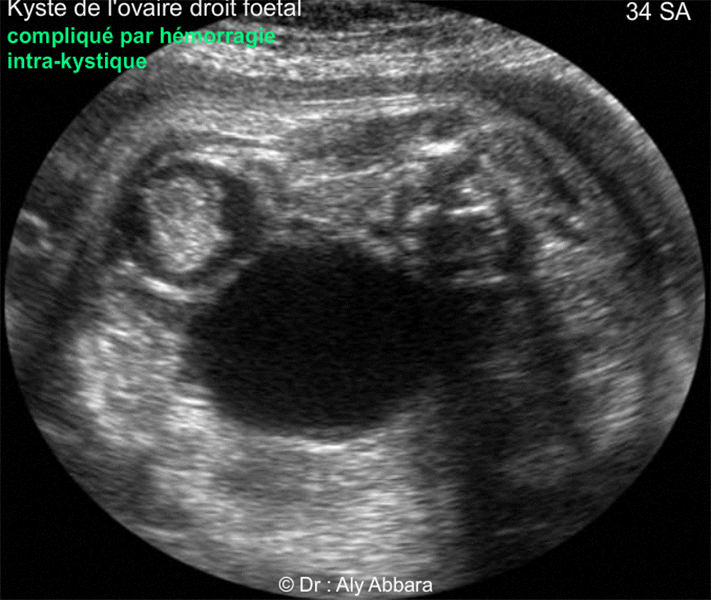

| L'hémorragie intrakystique du kyste de l'ovaire fœtal se manifeste par le changement de son aspect, il augmente de volume et son contenu devient hétéro-échogène, avec parfois la présence caillots sanguins rétractiles et la formation d'échos déclives, c'est-à-dire de niveau fluide-fluide par la déposition de caillots sanguins au fond du kyste. Quand l'hémorragie intra-kystique est importante, le kyste prend l'aspect d'un hématome solide et organisé L'hémorragie intrakystique est souvent secondaire, suite à une torsion ovarienne. |